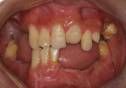

牙齒缺失

成人牙齒缺失,可能會有不同的原因。常見的缺牙原因,可能是由於早期的齲齒或意外事故所造成。

牙齒缺失最常見的現象是上排側面的牙齒缺少,缺失的牙齒通常是門齒、前臼齒及第三臼齒。另一種缺牙原因可能是牙齒受到壓阻,也就是無法長出到牙齦上面來。這會造成許多問題。最常發生受到壓阻無法長出來的牙齒是上犬齒、前臼齒及智齒。

部分缺牙包括單個或多個牙的缺失。單個牙的缺失一般好發於恆牙,可對稱發生也可單側發生,最常見的牙位是第三磨牙。 另外,上頜的側切牙和上下頜的第二前磨牙先天缺失率也相對較高,且常為對稱發生。個別乳牙的缺失極少發生。上頜側切牙、下頜側切牙和尖牙也可發生。其原因尚不十分清楚,一般認為有家族遺傳因素,個別可能是常染色體顯性遺傳。